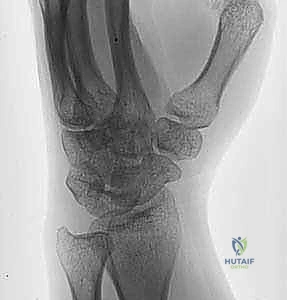

- الأشعة السينية (X-rays): يتم أخذ صور بأوضاع مختلفة (أمامي خلفي، جانبي، ومائل) لرؤية الكسر بوضوح. أحياناً يكون الكسر دقيقاً جداً ولا يظهر إلا من خلال علامة "وسادة الدهون المرفوعة" (Positive Fat Pad Sign) التي تشير إلى وجود نزيف داخل المفصل.

- الأشعة المقطعية (CT Scan): في حالات الكسور المفتتة أو المعقدة، يطلب الدكتور هطيف إجراء أشعة مقطعية ثلاثية الأبعاد (3D CT) لبناء تصور هندسي دقيق للكسر، مما يساعده في تخطيط العملية الجراحية واختيار الشرائح والمسامير المناسبة قبل دخول غرفة العمليات.